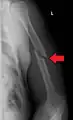

A transverse fracture of the humerus shaft

| Midshaft humerus fracture with callus formation | |